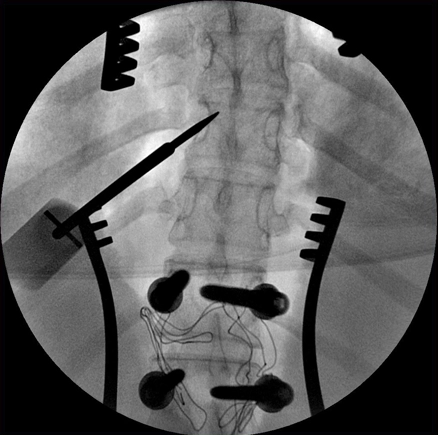

Цифровые изображения с матрицей 1024x1024 помогут увидеть мелкие детали

Визуализируйте мелкие детали сложных структур, просто наведите аппарат и нажмите кнопку экспозиции, и цифровая цепи формирования изображений с матрицей 1024x1024 сделает всю сложную работу. Эта цифровая цепь включает в себя усовершенствованные средства шумоподавления и подчеркивания контуров в двумерных изображениях. Благодаря высококачественным изображениям можно быстро визуализировать сложные костные структуры для более точной установки имплантатов.

MetalSmart — автоматическое исключение артефактов от металла

Артефакты от имплантатов и других металлических объектов могут скрывать анатомические структуры, затруднять визуализацию и снижать точность диагностики. Программа MetalSmart исключает артефакты от металла, не влияя на контрастность изображений и позволяя избежать увеличения дозы рентгеновского излучения, что происходит при наличии металлических объектов в поле исследования.